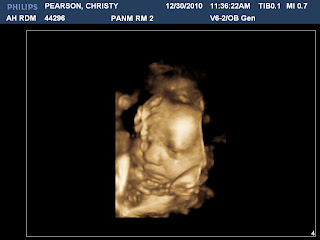

Here is a picture of the little one at 33 weeks, 4 days. He measures nearly 35 weeks, weighing in at 5.5 lbs. and 17.4 inches so far. We can't wait to meet you little buddy. I wonder who you will resemble most.... Until we meet, I hope you enjoy this wonderful place you are sharing with your big brother Chase and will be ready to tell me all about it in a few weeks!